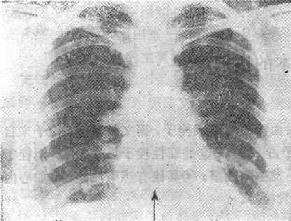

图116-1 肺梗死

(二)有胸片可以正确地解释肺核素扫描的图象

(三)胸片可以显示肺栓塞的某些X线表现 ①一侧膈肌升高,大约有一半的急性肺栓塞的患者有此表现(肺容积的减少);②约有30%~50%的肺栓塞患者有一过性的肺实质浸润;③肺不张(约20%),但机制不清;④胸膜渗出,有1/3的患者出现;⑤有两个特异性的X线表现:Hampten’s驼峰征,为一个肺内的实变征,呈圆形圆顶状轮廓,顶部指向肺门,位于肺肋膈角区或后肋膈窦区;Wamptark’s征,栓塞侧近侧肺动脉扩张而远侧缺乏之灌注(无血管区),这两种特异的征象是很少见的;⑥肺动脉主干扩张、肺动段突出,甚至右心室增大。